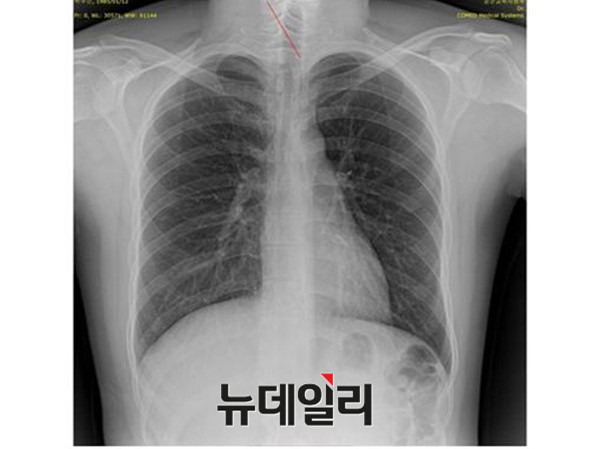

박원순 서울시장의 아들 박주신씨 병역비리 의혹과 관련돼, 세계적으로 권위를 인정받고 있는 해외 의학자들이, 박주신씨 명의의 엑스레이 사진에 대한 판독결과, 피사체를 동일인으로 볼 수 없다는 의학적 소견을 내놨다.

박주신씨의 신체를 촬영한 엑스레이는 모두 3개가 존재한다. 첫 번째는 2011년 12월 촬영된 자생병원 엑스레이이며, 두 번째는 박주신씨가 2011년 8월 공군에 입소하면서 본인 확인 후 촬영한 엑스레이다. 세 번째 엑스레이는 지난해 7월 주신씨가 영국 출국에 앞서 비자 발급을 위해 연세대 세브란스병원에서 새로 촬영한 것이다.

이들 3개의 엑스레이 가운데 자생병원 엑스레이에 대해서는, 주신씨 본인이 아닌 대리신검자가 촬영한 것이라는 의혹을 받고 있다.

의혁투가 공개한 소견서는 아시아근골격학회 사무총장을 맡고 있는 스리 안드리아니 우토모 교수가 작성한 것으로, 박주신씨가 지난해 7월, 영국 출국 비자를 발급받기 위해 연세대 세브란스병원에서 촬영한 엑스레이(A)와, 2011년 12월 촬영된 자생병원 엑스레이(B)를 동일인의 것으로 볼 수 없다는 의학적 소견을 담고 있다.

의혁투는 아시아근골격학회에 보낸 의견 조회서에서, 박주신씨 명의의 두 엑스레이에서 나타나는 대표적 차이점인 ▲경추7번 및 흉추1번 척추골(극상돌기) ▲우측 늑골 1번의 ‘석회화 현상’ ▲전체적인 흉곽의 형태 ▲쇄골 형태의 차이 ▲하행 대동맥의 음영 등에 대해 질의했다.

이에 대해 우토모 교수는 위의 모든 항목에서, “두 엑스레이는 서로 다르다”는 견해를 분명히 밝혔다.

반면 지난해 12월부터 시작된 양승오 박사 등 시민 7명에 대한 공직선거법 위한 공판을 통해 새롭게 밝혀진, 박주신씨의 ‘공군훈련소 입소 당시 엑스레이’(촬영일자 2011년 8월 30일, 이하 공군 엑스레이)와, 주신씨가 ‘비자발급을 위해 촬영한 세브란스병원 엑스레이’(촬영일자 2014년 7월 31일, 이하 비자발급용 엑스레이)는 각각 박주신씨 본인의 신체를 촬영한 것으로 받아들여지고 있다.

- ▲ 박주신씨가 지난해 7월 비자발급을 위해 촬영한 엑스레이. ⓒ 뉴데일리DB